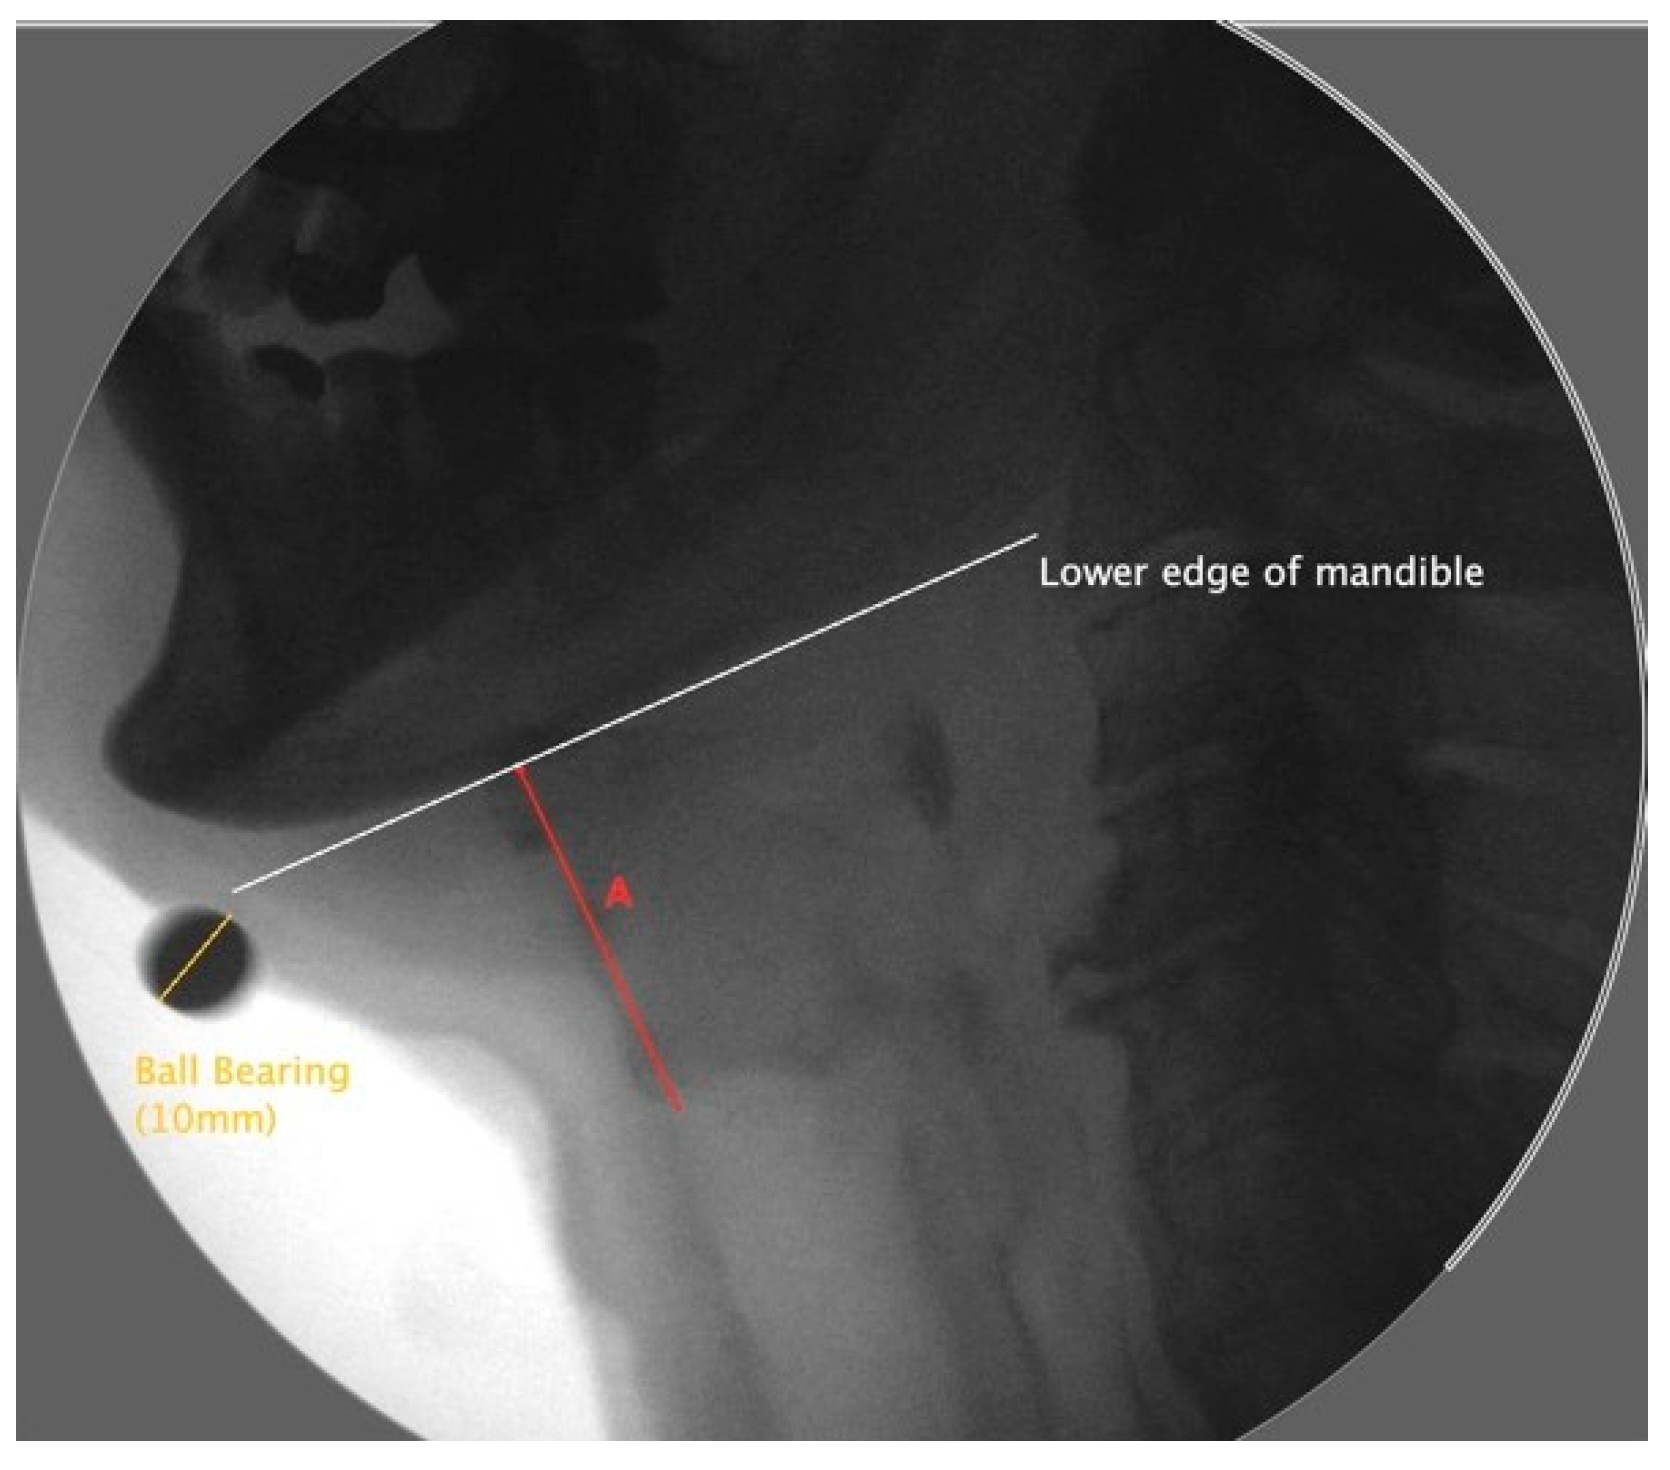

Frame-by-frame analysis was used to determine and produce still images of the laryngeal resting and maximum displacement positions. The images were analyzed and scaled using ImageJ. A line along the lowest edge of the mandible was used as a reference point. Measurements of the larynx were taken between the superior anterior corner of the air column and the reference line of the mandible. Laryngeal elevation was defined as the distance of the larynx and the mandible measured in the resting frame subtracted from the laryngeal mandible distance measured from the frame of maximal excursion, as shown in Figure 3 [34].

Figure 3.

Lateral view of a videofluoroscopic frame displaying a maximally elevated larynx with a tangent line (white) to the mandible. Line A (red), perpendicular to the tangent line, is the measure between the larynx and mandible.